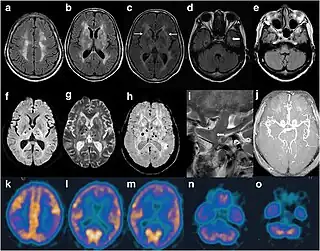

Imágenes craneales de un paciente FFI. En la resonancia magnética hay señales anormales en el área subcortical frontoparietal bilateral. La ARM mostró ramas distales más pequeñas de las arterias cerebrales.